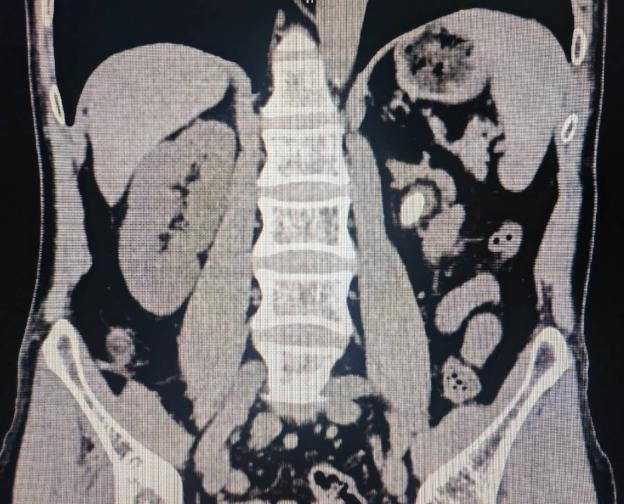

术前影像学检查: